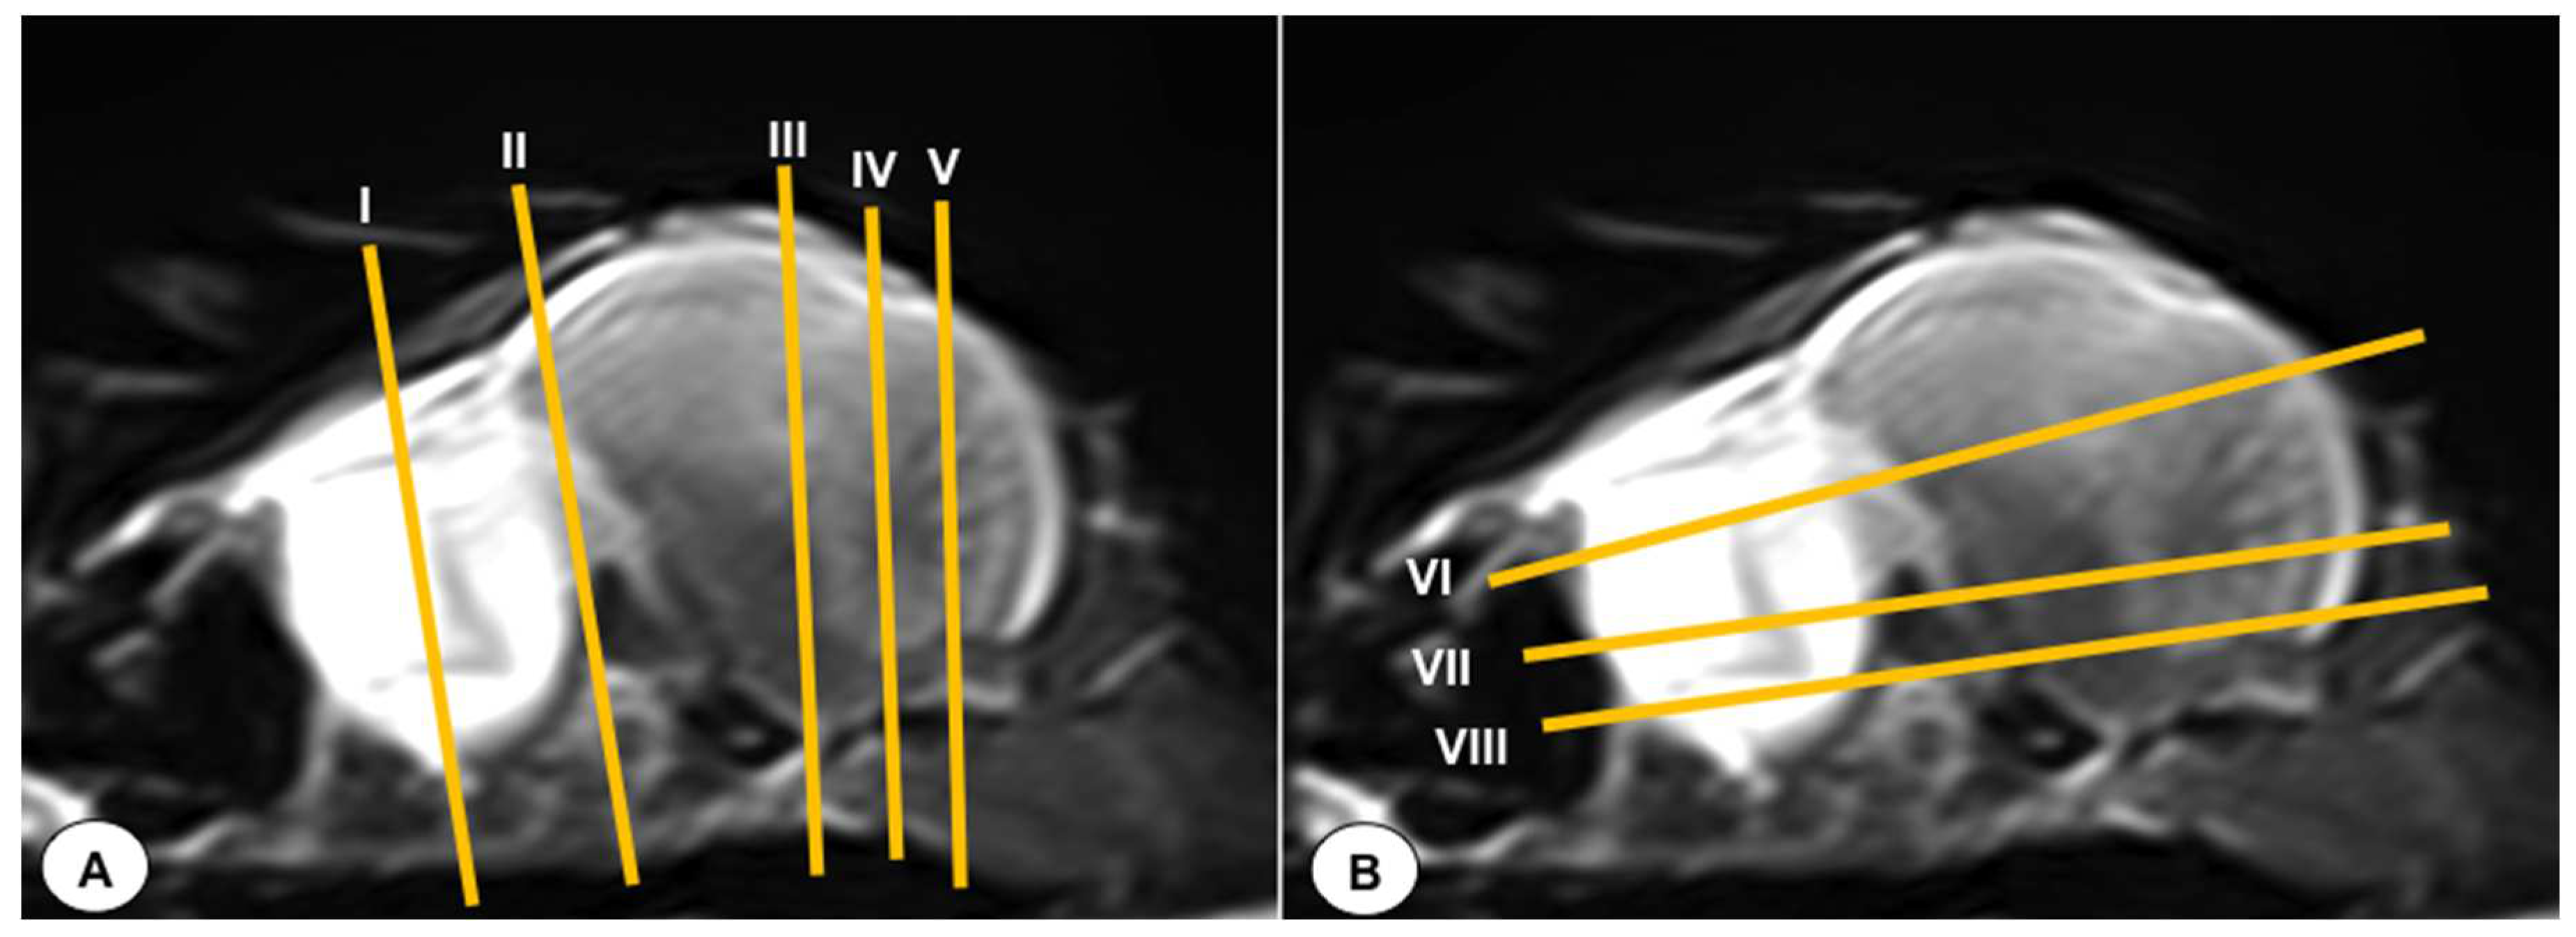

Figure 1. T2-weighted MR sagittal image of the head of an Atlantic puffin (Fratercula arctica). The vertical (labeled as A) and horizontal (labeled as B) lines correspond to the approximate level of the respective transverse and dorsal slices.